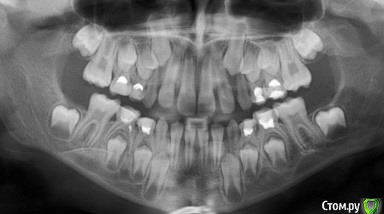

Леголич Опубликовано 20 апреля, 2018 Поделиться Опубликовано 20 апреля, 2018 Доброго дня. Вопрос по нижнему правому 5 молочному моляру. Дочь пожаловалась на боль при накусывании, есть не могла. Сделали снимок- воспаления нет, но решили поменять пломбу. Поменяли, поставили со слов врача лекарство и пломбу Глоссит в 5 вечера. На следующий день утром Т 37.2, небольшой отек щеки, покраснение слизистой десны и щеки. Боли нет. При накусывании не сильно. Жалобы на зуд. Получила Фенистил - не помогло. Т 38.3. Поехали к врачу. Сделали снимок( прикреплен ниже). Ничего менять не стали. Домой и наблюдать 3 дня. Вечером 37.5 без лекарств. Ночью не спала- зуд. Утром Т 37.2, отек щеки вырос в 3 раза. Боли нет, зуд несильный. Днём Т 38.3 опять. Общее состояние удовлетворительное. Вечером опять едем к врачу. Но я уже сомневаюсь. Мне важно знать мнение другого врача.Вопрос: это может быть аллергической реакцией на стомматериалы? Раньше зубы лечили, но пломбы ставили светоотв и вроде без лекарств. Подобного не было ни разу. Спасибо. Ссылка на комментарий